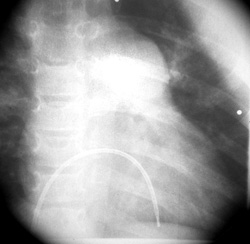

Καθετηριασμός καρδιάς: πιέσεις στην πνευμονική κυκλοφορία σχεδόν ίσες με της

συστηματικής (96% της συστηματικής), μειωμένο SpO2 του αρτηριακού αίματος (93%)

χωρίς διαφυγή αίματος από την αριστερή στη δεξιά κοιλία, υπερτροφία της δεξιάς

κοιλίας και διάταση του στελέχους της πνευμονικής και των κλάδων της (εικόνα

2).

Εικόνα 2. Καθετηριασμός καρδιάς

της ασθενούς. Υπερτροφία δεξιάς κοιλίας και διάταση του στελέχους της πνευμονικής

αρτηρίας και των κλάδων της.